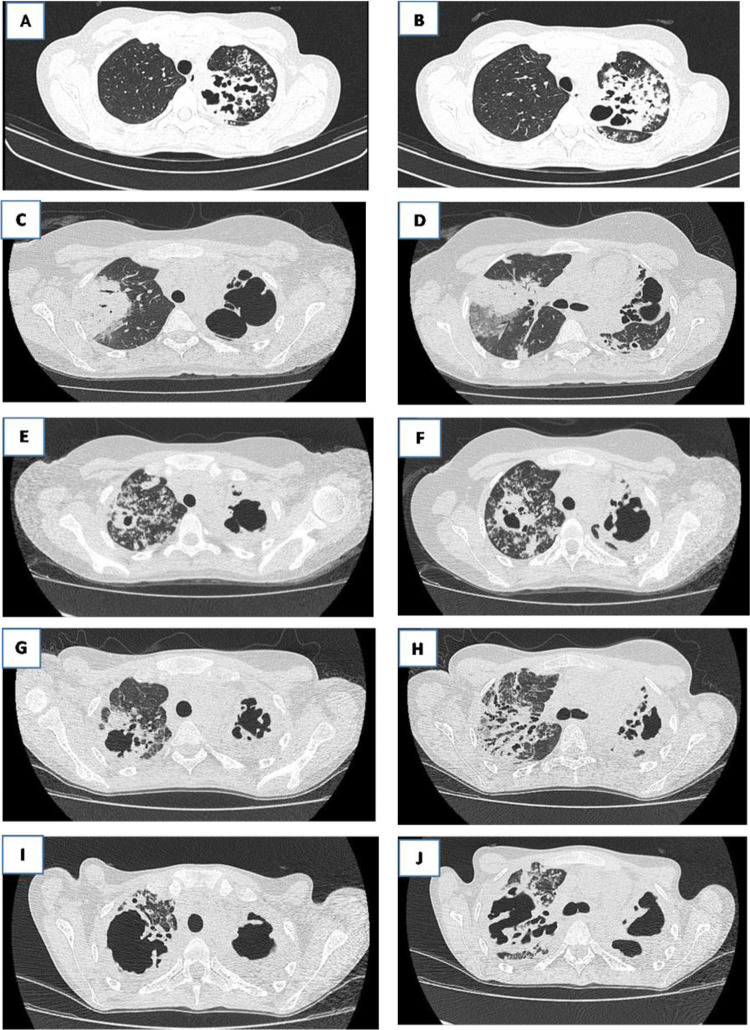

Tuberculosis (TB) is a global public health concern and a leading cause of death. Its persistence occurs mainly because barriers in the care cascade are not being fully addressed. Healthcare professionals and scientists have been addressing treatment challenges such as abandonment and irregular drug intake via strategies such as directly observing treatment and singular therapeutic projects to improve adherence. However, while protocols and guidelines advocate these strategies, their implementation requires a broader approach from healthcare teams. This article examines the importance of such strategies in clinical TB management and analyzes an unfavorable outcome in an immunocompetent patient treated for pulmonary tuberculosis (PTB) from 2017 to 2022. After recurrence and treatment, the patient continued to have persistent acid-fast bacilli in the sputum, positive cultures for Mycobacterium tuberculosis, and progressive lung lesions, despite receiving the recommended treatment. Although categorized as having an intermediate risk of treatment abandonment, the patient faced challenges, such as the COVID-19 pandemic, pregnancy, and being diagnosed with COVID-19. After therapeutic failure and the loss of beneficial prospects, palliative care was initiated. This case illustrates the complexities of managing TB in patients with recurrent disease despite apparent adherence to treatment. After reassessing the risk of abandonment score, the patient was categorized as high-risk. This underscores the importance of singular therapeutic projects, such as psychological support for high-risk or intermediate patients, to prevent negative outcomes. This case reinforces the critical need for comprehensive patient-centered approaches to successfully treat and manage TB.